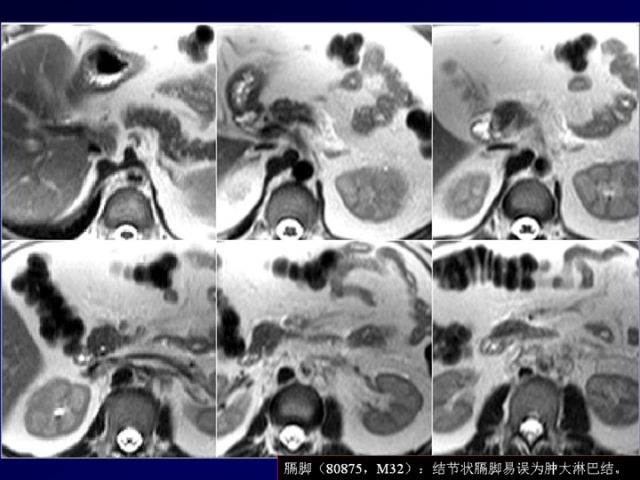

膈肌角解剖及常见变异

作者:王俭 上海长征医院